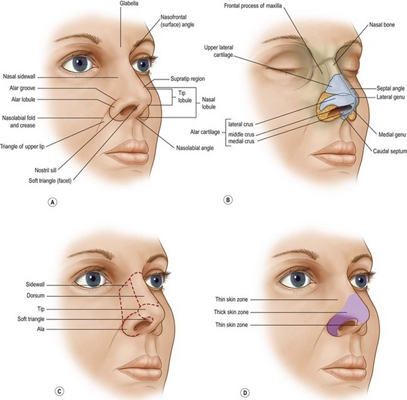

鼻中隔彎曲手術圖解 (49)

鼻中隔彎曲手術圖解 (5)

鼻中隔彎曲手術圖解 (50)

鼻中隔彎曲手術圖解 (6)